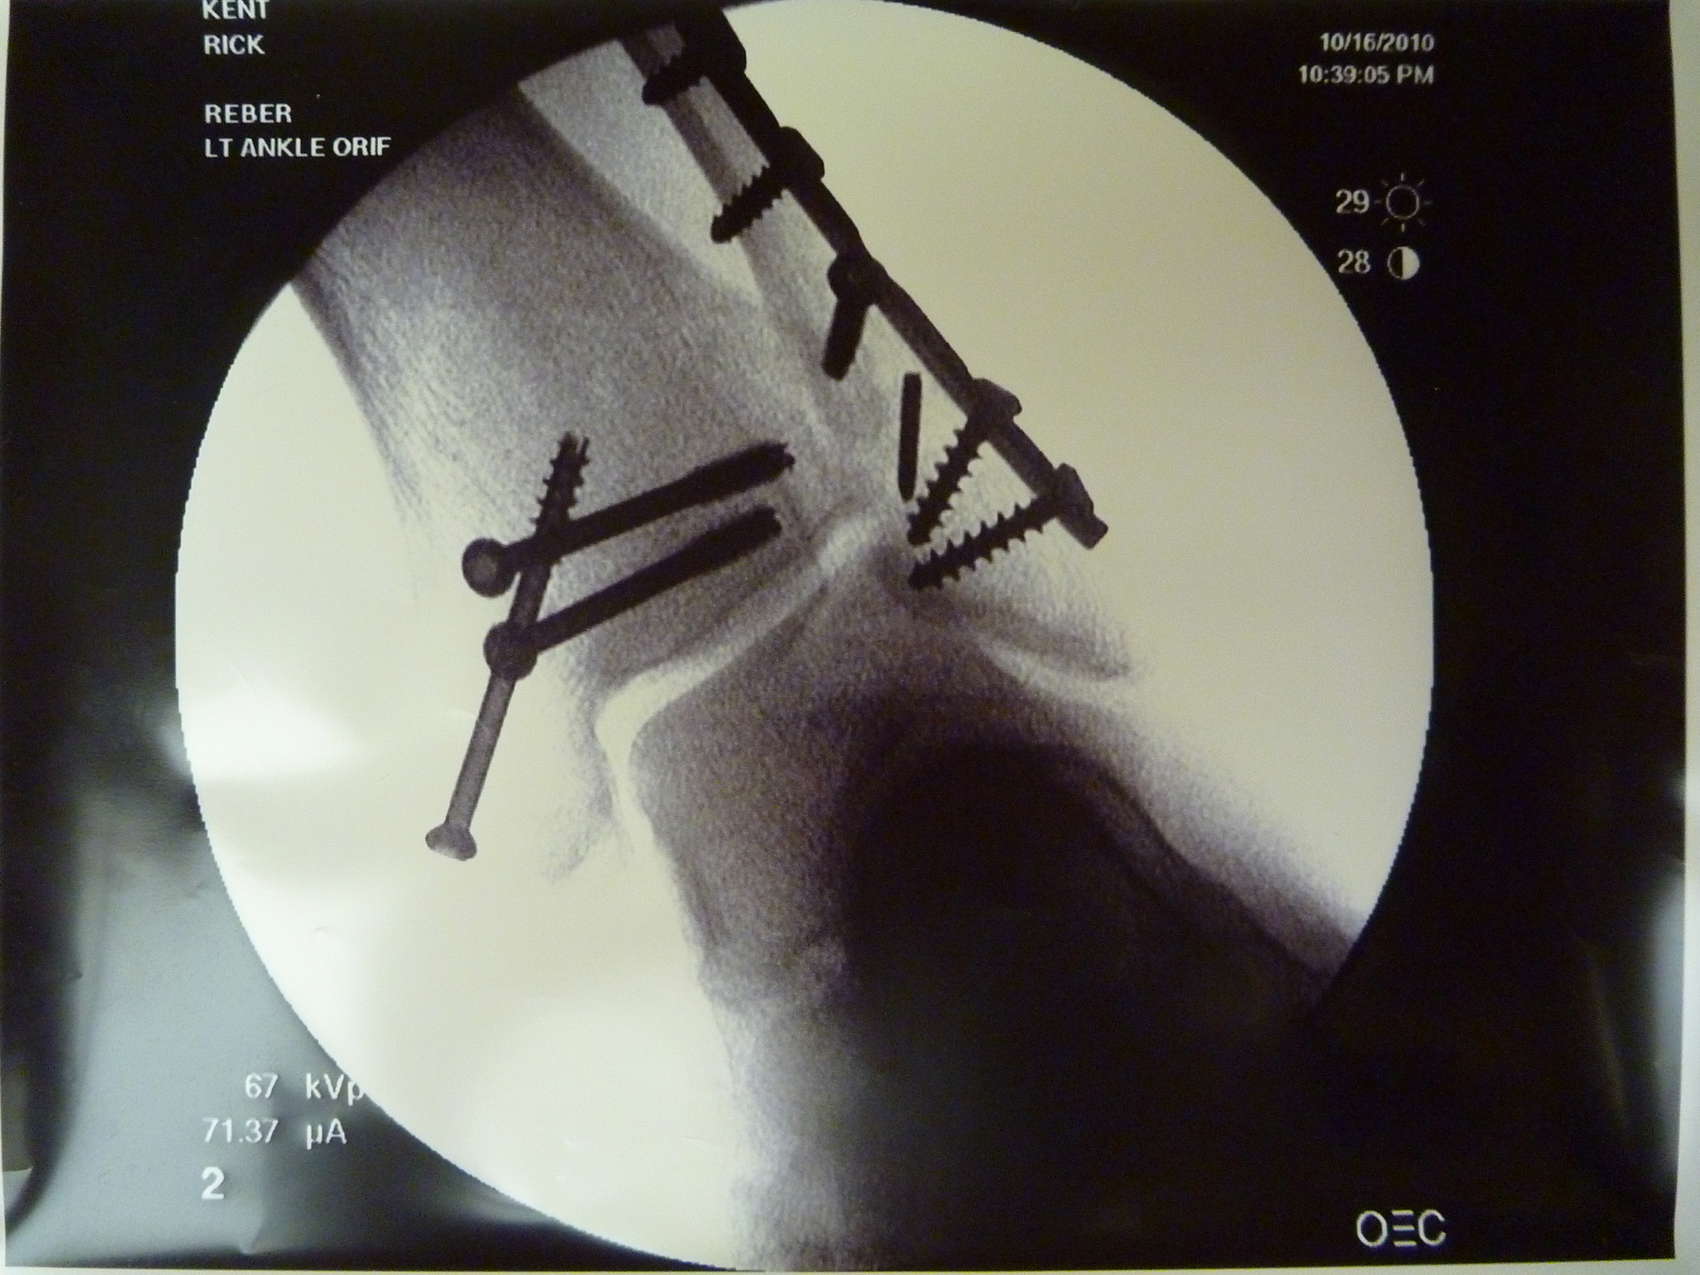

Album: Accident Photos: X-rays

Album Date

10/16/2010